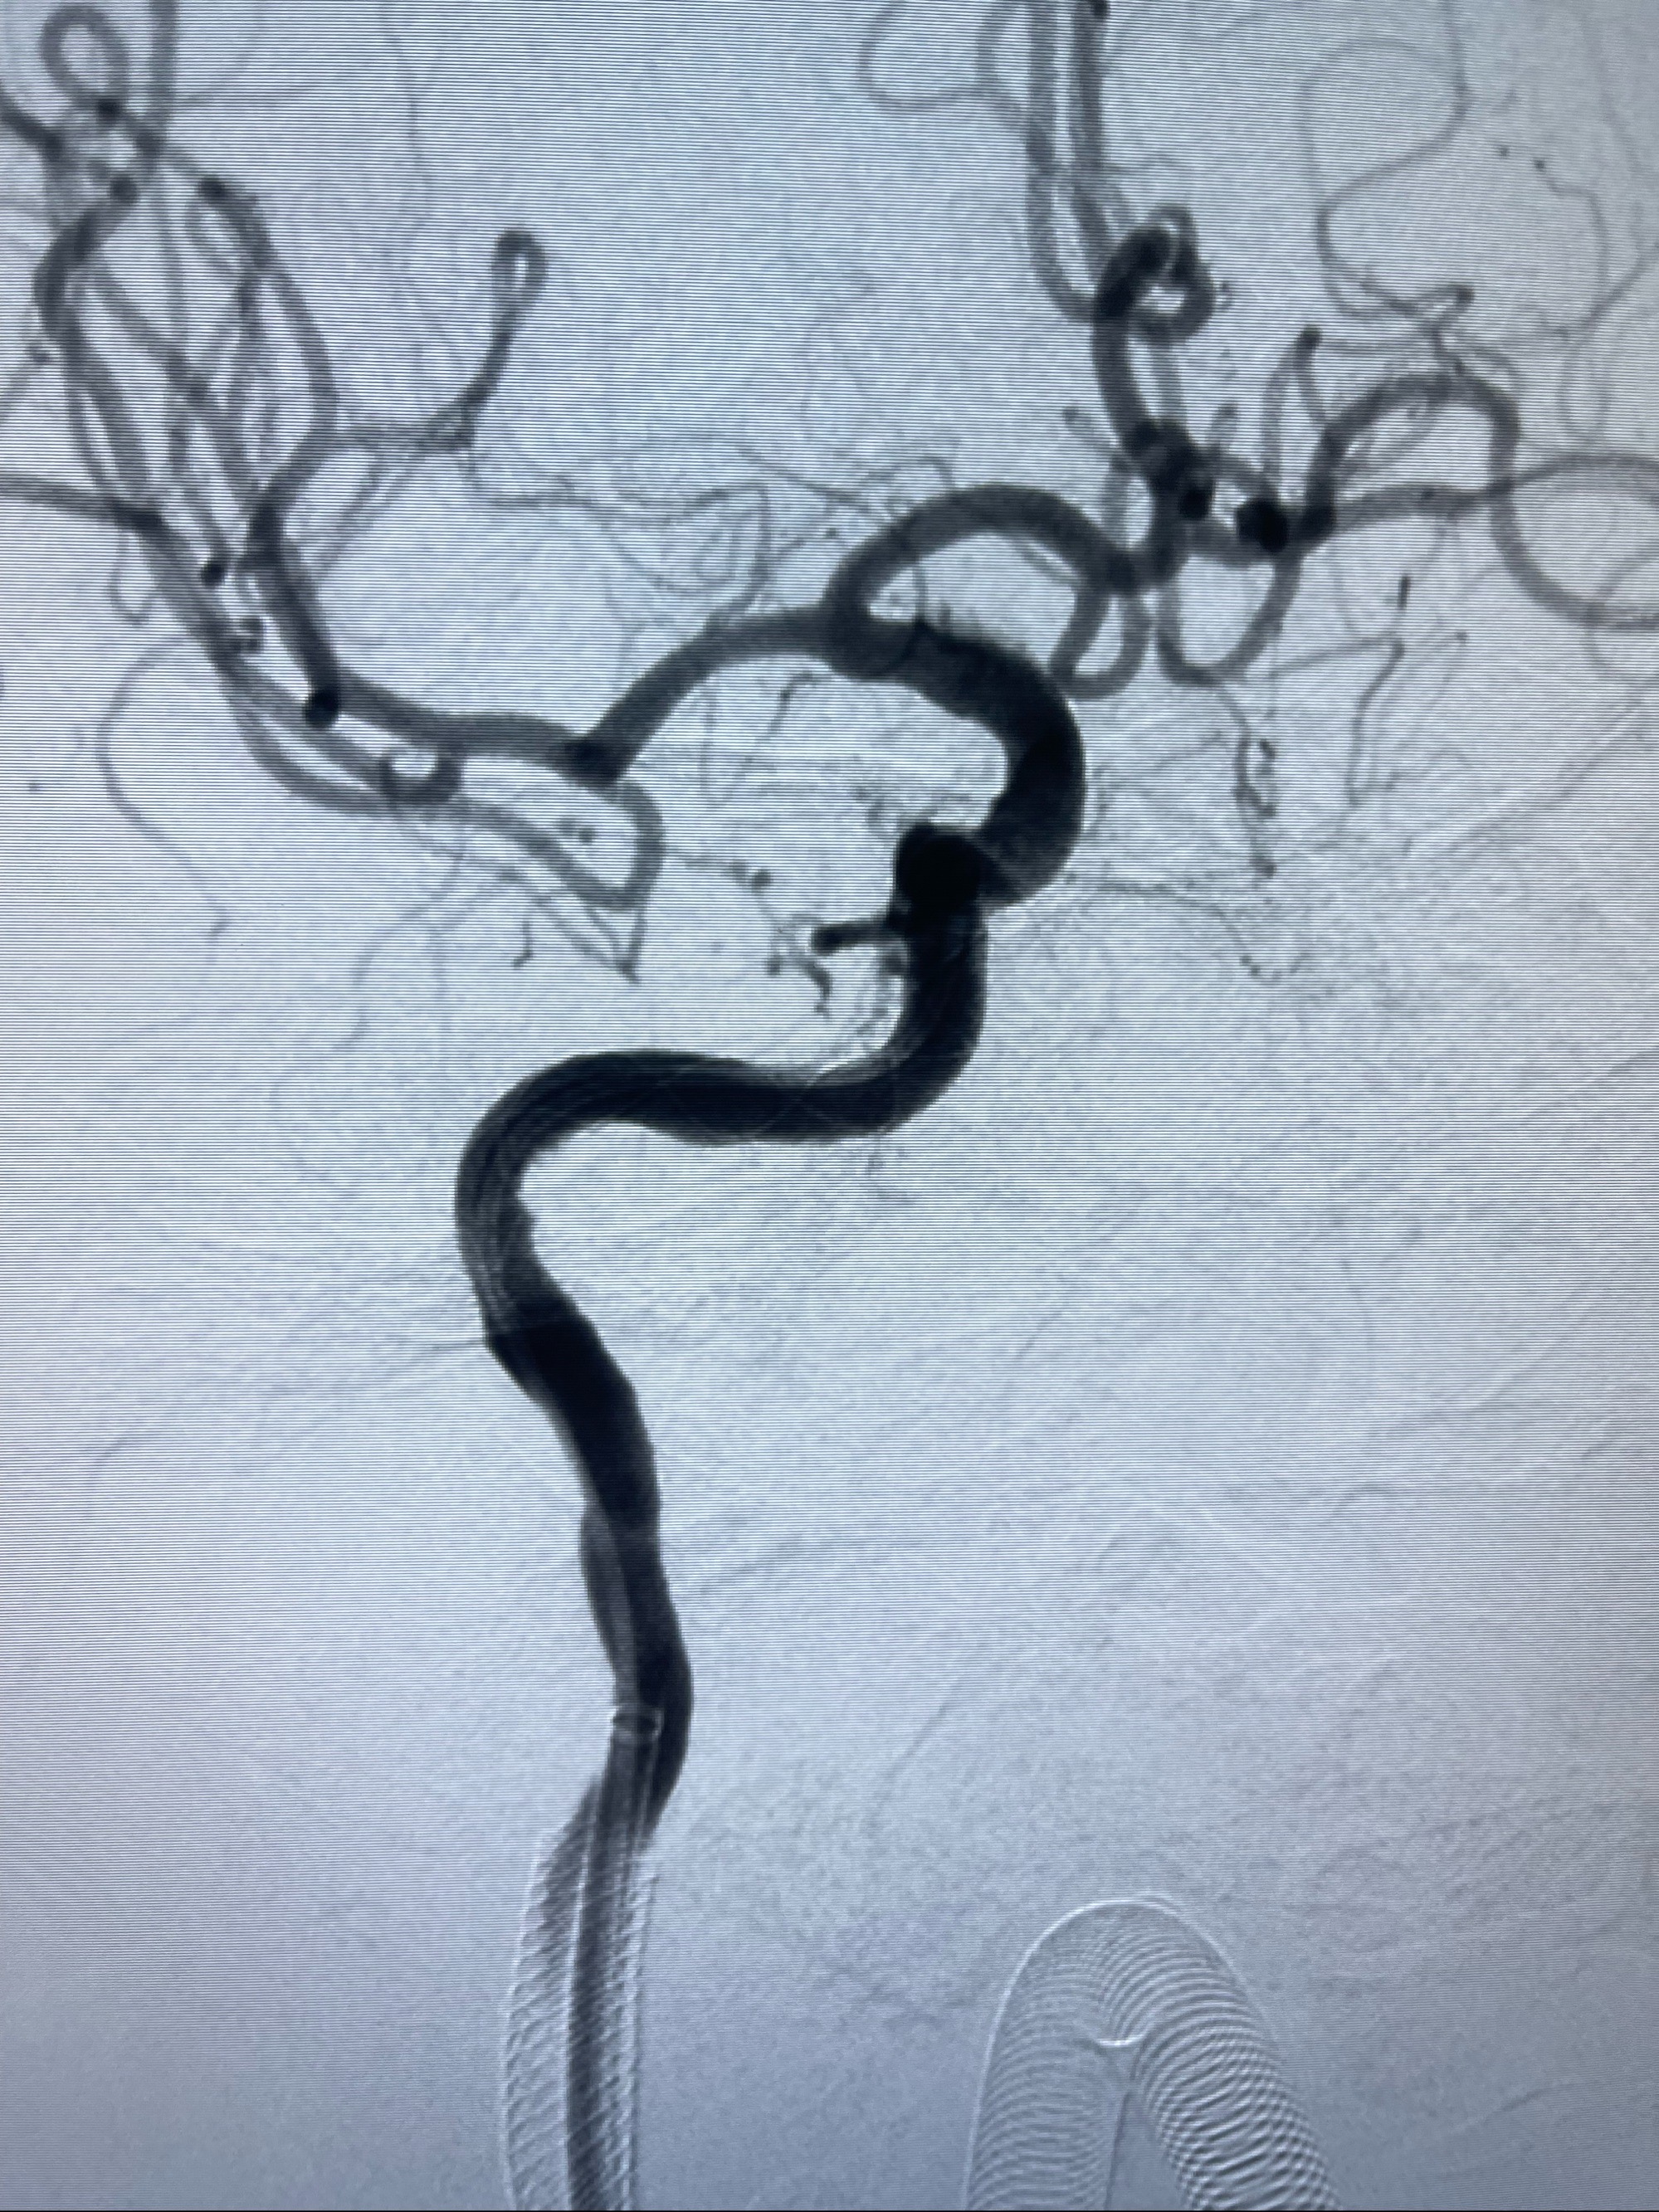

泄除球囊造影显示局部管腔扩张佳

后移球囊至颈段狭窄段,以8-12个大气压扩张,持续30s后泄除球囊

即刻造影显示狭窄扩张佳

重新行“路径图”,支架导管在微导丝引导下超选择性插入至右侧颈内动脉眼段,4.5-50mmLeo支架释放,远心端位于海绵窦段,近心端位于岩骨段狭窄段以近

即刻造影显示支架贴壁佳